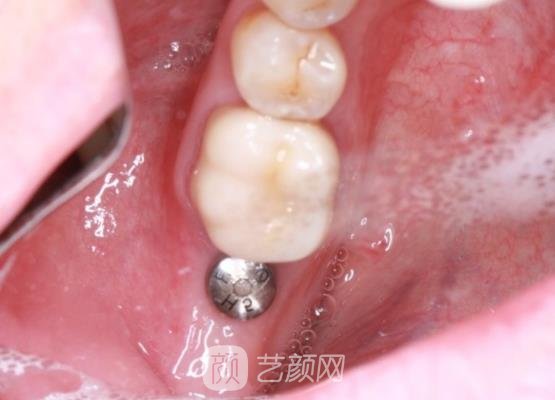

接下来手术就开始了,打麻药的时候是有一些疼的,这个时候我也突然紧张了起来,后来随着时间的推移麻药有了成果以后,疼痛的感觉也就基本上没有了,手术也没有耽误我很多的时间,短短几个小时以后手术就结束了。

手术刚结束时,我的牙龈处有一些肿胀的情况,还很疼,医生告诉我这些现象比较正常,然后给我开了一些消炎药让我定时服用,吃了消炎药以后果然疼痛的感觉缓解了很多,基本上没有了。

过了几个月以后,我的种植牙已经恢复的很自然了,就像是我自己的牙齿一样,而且口腔里面也没有出现什么不适的异物感,医生真的很负责,术后还很密切的关注我的恢复情况,及时的给了我康复的建议。